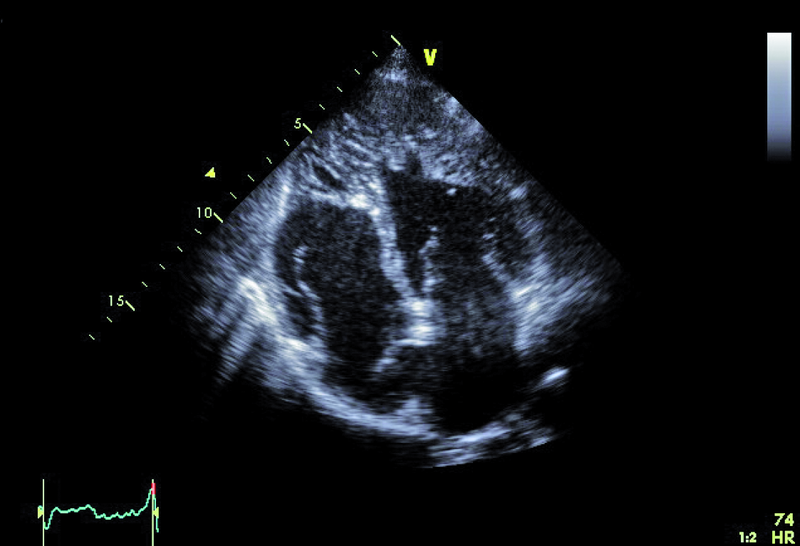

Kobieta, lat 36. Jakie patologie można rozpoznać na zamieszczonych rycinach?

4. Zwyrodnienie gąbczaste mięśnia prawej i lewej komory (ryc. 4, 5).

5. Tętniak przegrody międzyprzedsionkowej (ryc. 4-6).